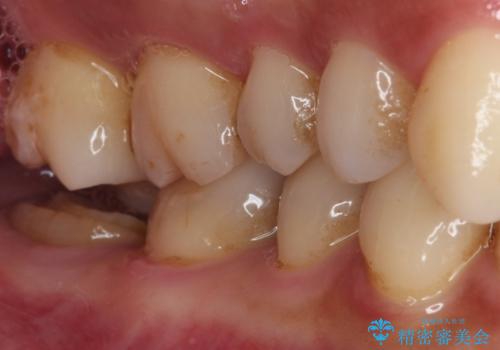

- かかりつけ医にて、歯の高さが不足しているためセラミッククラウンの装着はできないと言われたとのことで来院された患者様です。

診察したところ、確かに歯の高さは不足していましたが、土台の立て直しや歯の削り方を調整することでオールセラミッククラウンでも補綴可能と思われました。

ただし、クラウンの厚みは極力薄くした方が維持力が増すため、高強度のフルジルコニアクラウンにて補綴治療することとしました。

仮歯が途中外れることもなく、無事に補綴治療を行うことができました。

歯石や磨き残しなどが多いため、今後クリーニングを行っていきます。